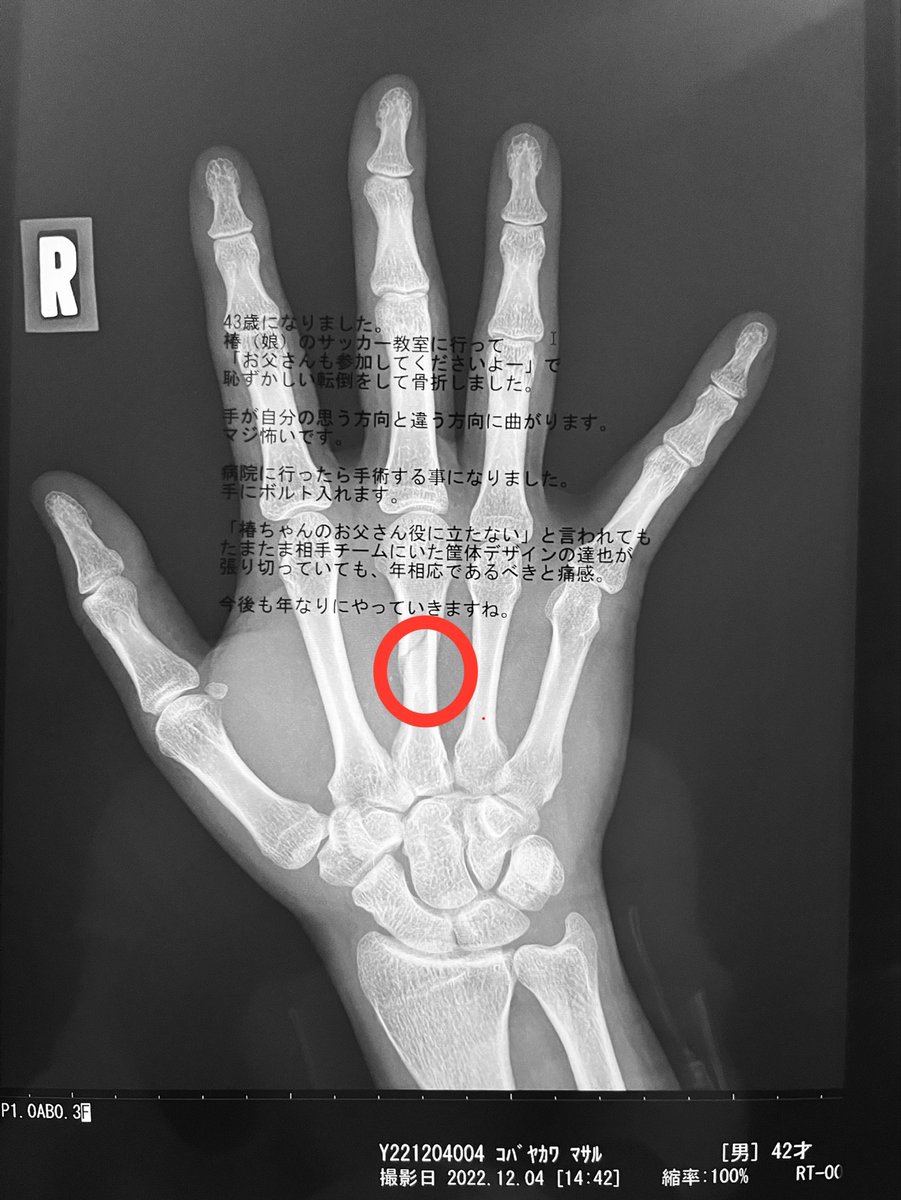

43歳になりました。 情けない理由で骨を折りました。 世間では43歳からおじさんという認識らしいのですが まさしくな状況を痛感してます。 (全然、ゲームできません…) 今後は歳なりにがんばって行きますね…。 かなしい。